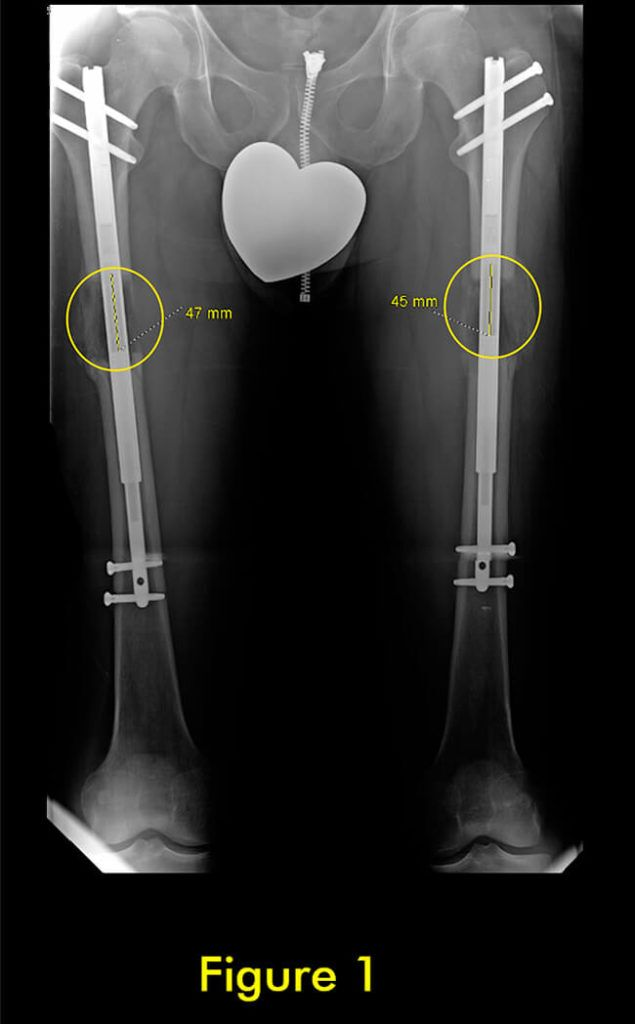

过早合并示意图1

图1:延长量细微差异

过早合并示意图2

图2:X光片确认诊断

随着胫骨的延长,腓骨也必须延长。植入式加长装置仅延长和固定胫骨。腓骨必须固定在胫骨上,以便它与胫骨一起拉长。如果腓骨固定不固定或固定不充分,它不会像胫骨那样拉长,并会导致严重的后果,包括脚踝半脱位和关节炎以及膝盖屈曲挛缩。

固定方法至关重要。许多外科医生只将腓骨的下端固定在胫骨上。这会导致腓骨过早巩固,并在其上端从胫骨向下拉和脱臼。固定腓骨两端很重要。大多数外科医生避免这样做,因为这在技术上很难做到。

我们为所有患者的腓骨两端固定。植入式加长时,腓骨必须用螺钉固定在胫骨上;上端有一个螺钉,下端有一个螺钉。螺钉的角度、水平、位置、直径和类型都很重要。一个常见的错误是将螺钉水平放入两块骨头之间。这不足以防止腓骨从脚踝处的胫骨上拉开。这是非常微妙的,即使脚踝腓骨长度的几毫米差异也会给患者带来短期和/或长期后果。切除腓骨的一部分以防止腓骨不分离是另一种应避免的常见方法。它会导致腓骨不愈合,从而导致胫骨以后出现应力性骨折。

此外,它通常不会阻止腓骨从胫骨上拉开。因此,腓骨并发症与植入式延长装置的类型无关,而是与外科医生选择将腓骨固定到胫骨的方法和切割腓骨的方法有关。腓骨愈合的范围可以从过早巩固到完全不愈合。后者通常不需要治疗,只要胫骨牢固愈合。前者需要重复腓骨截骨术。